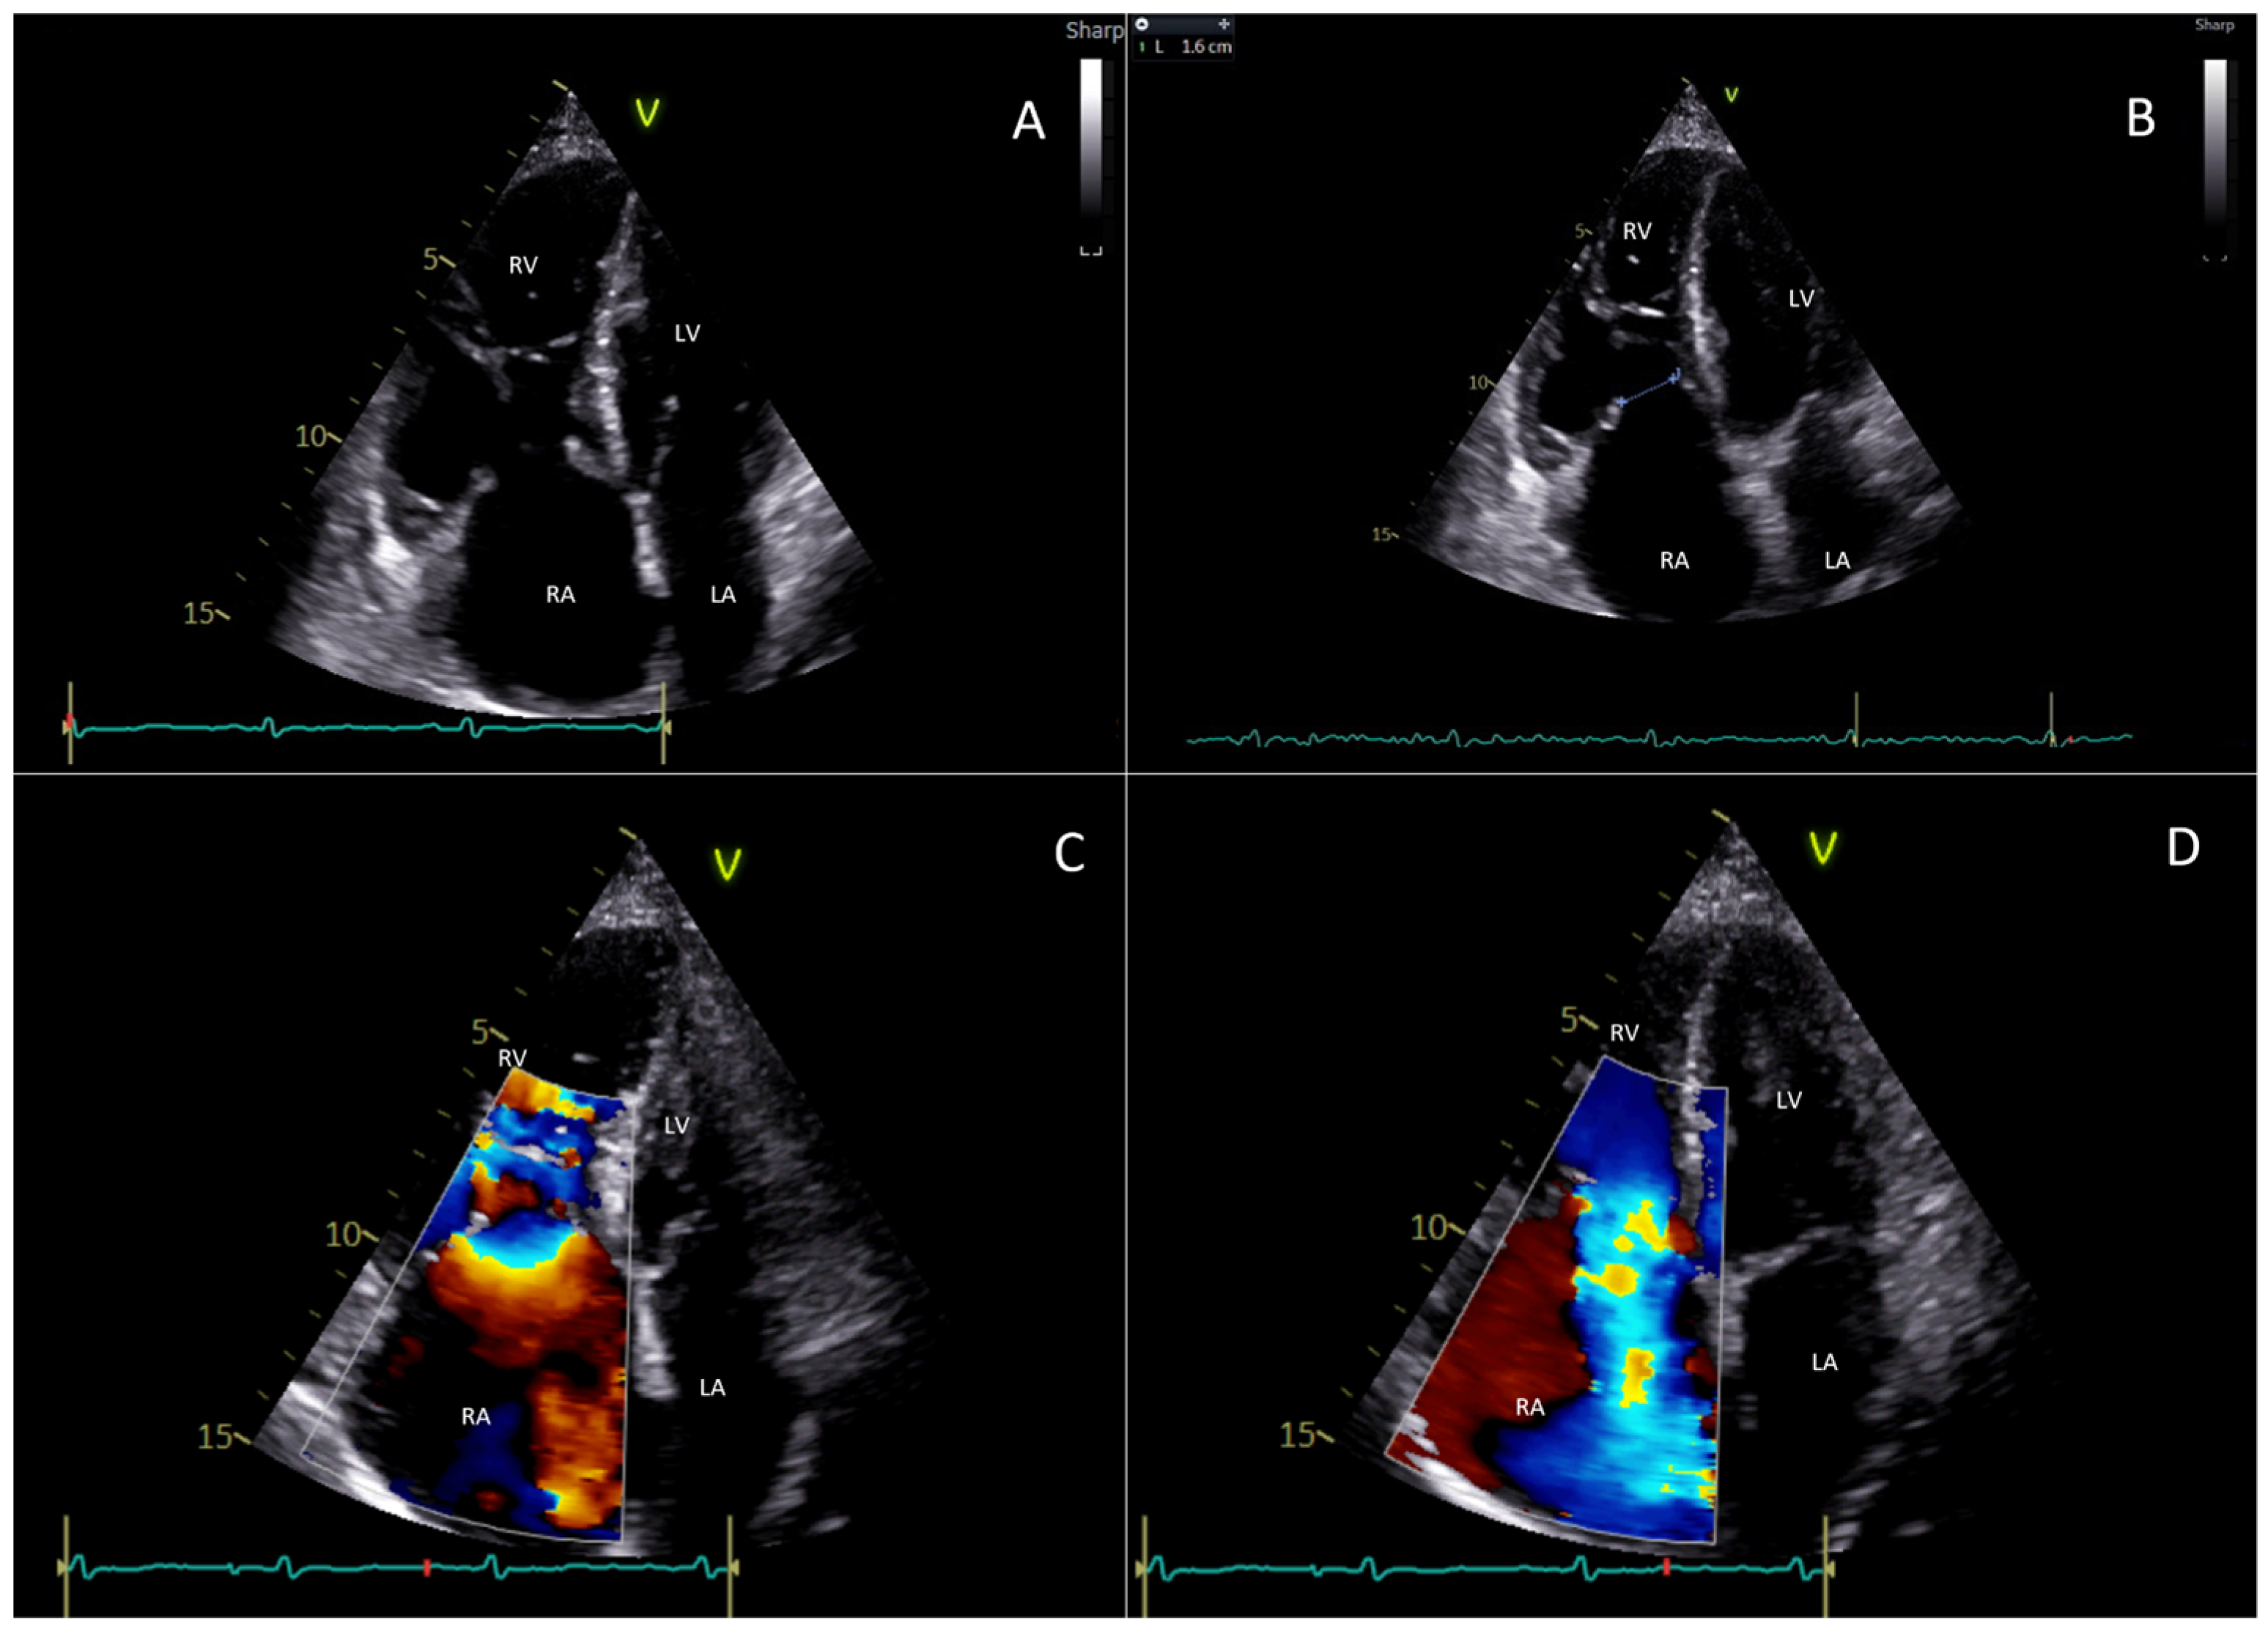

- Cammalleri, V.; Piscione, M.; De Luca, V.M.; Antonelli, G.; Cocco, N.; Nusca, A.; Gaudio, D.; Nobile, E.; Coletti, F.; Bianchi, A.; et al. Carcinoid Pulmonary Valve Stenosis: Multimodality Imaging and Transcatheter Valve Implant with Prestenting Technique. Circ. Cardiovasc. Imaging 2024, 18, e016785. [Google Scholar] [CrossRef] [PubMed]